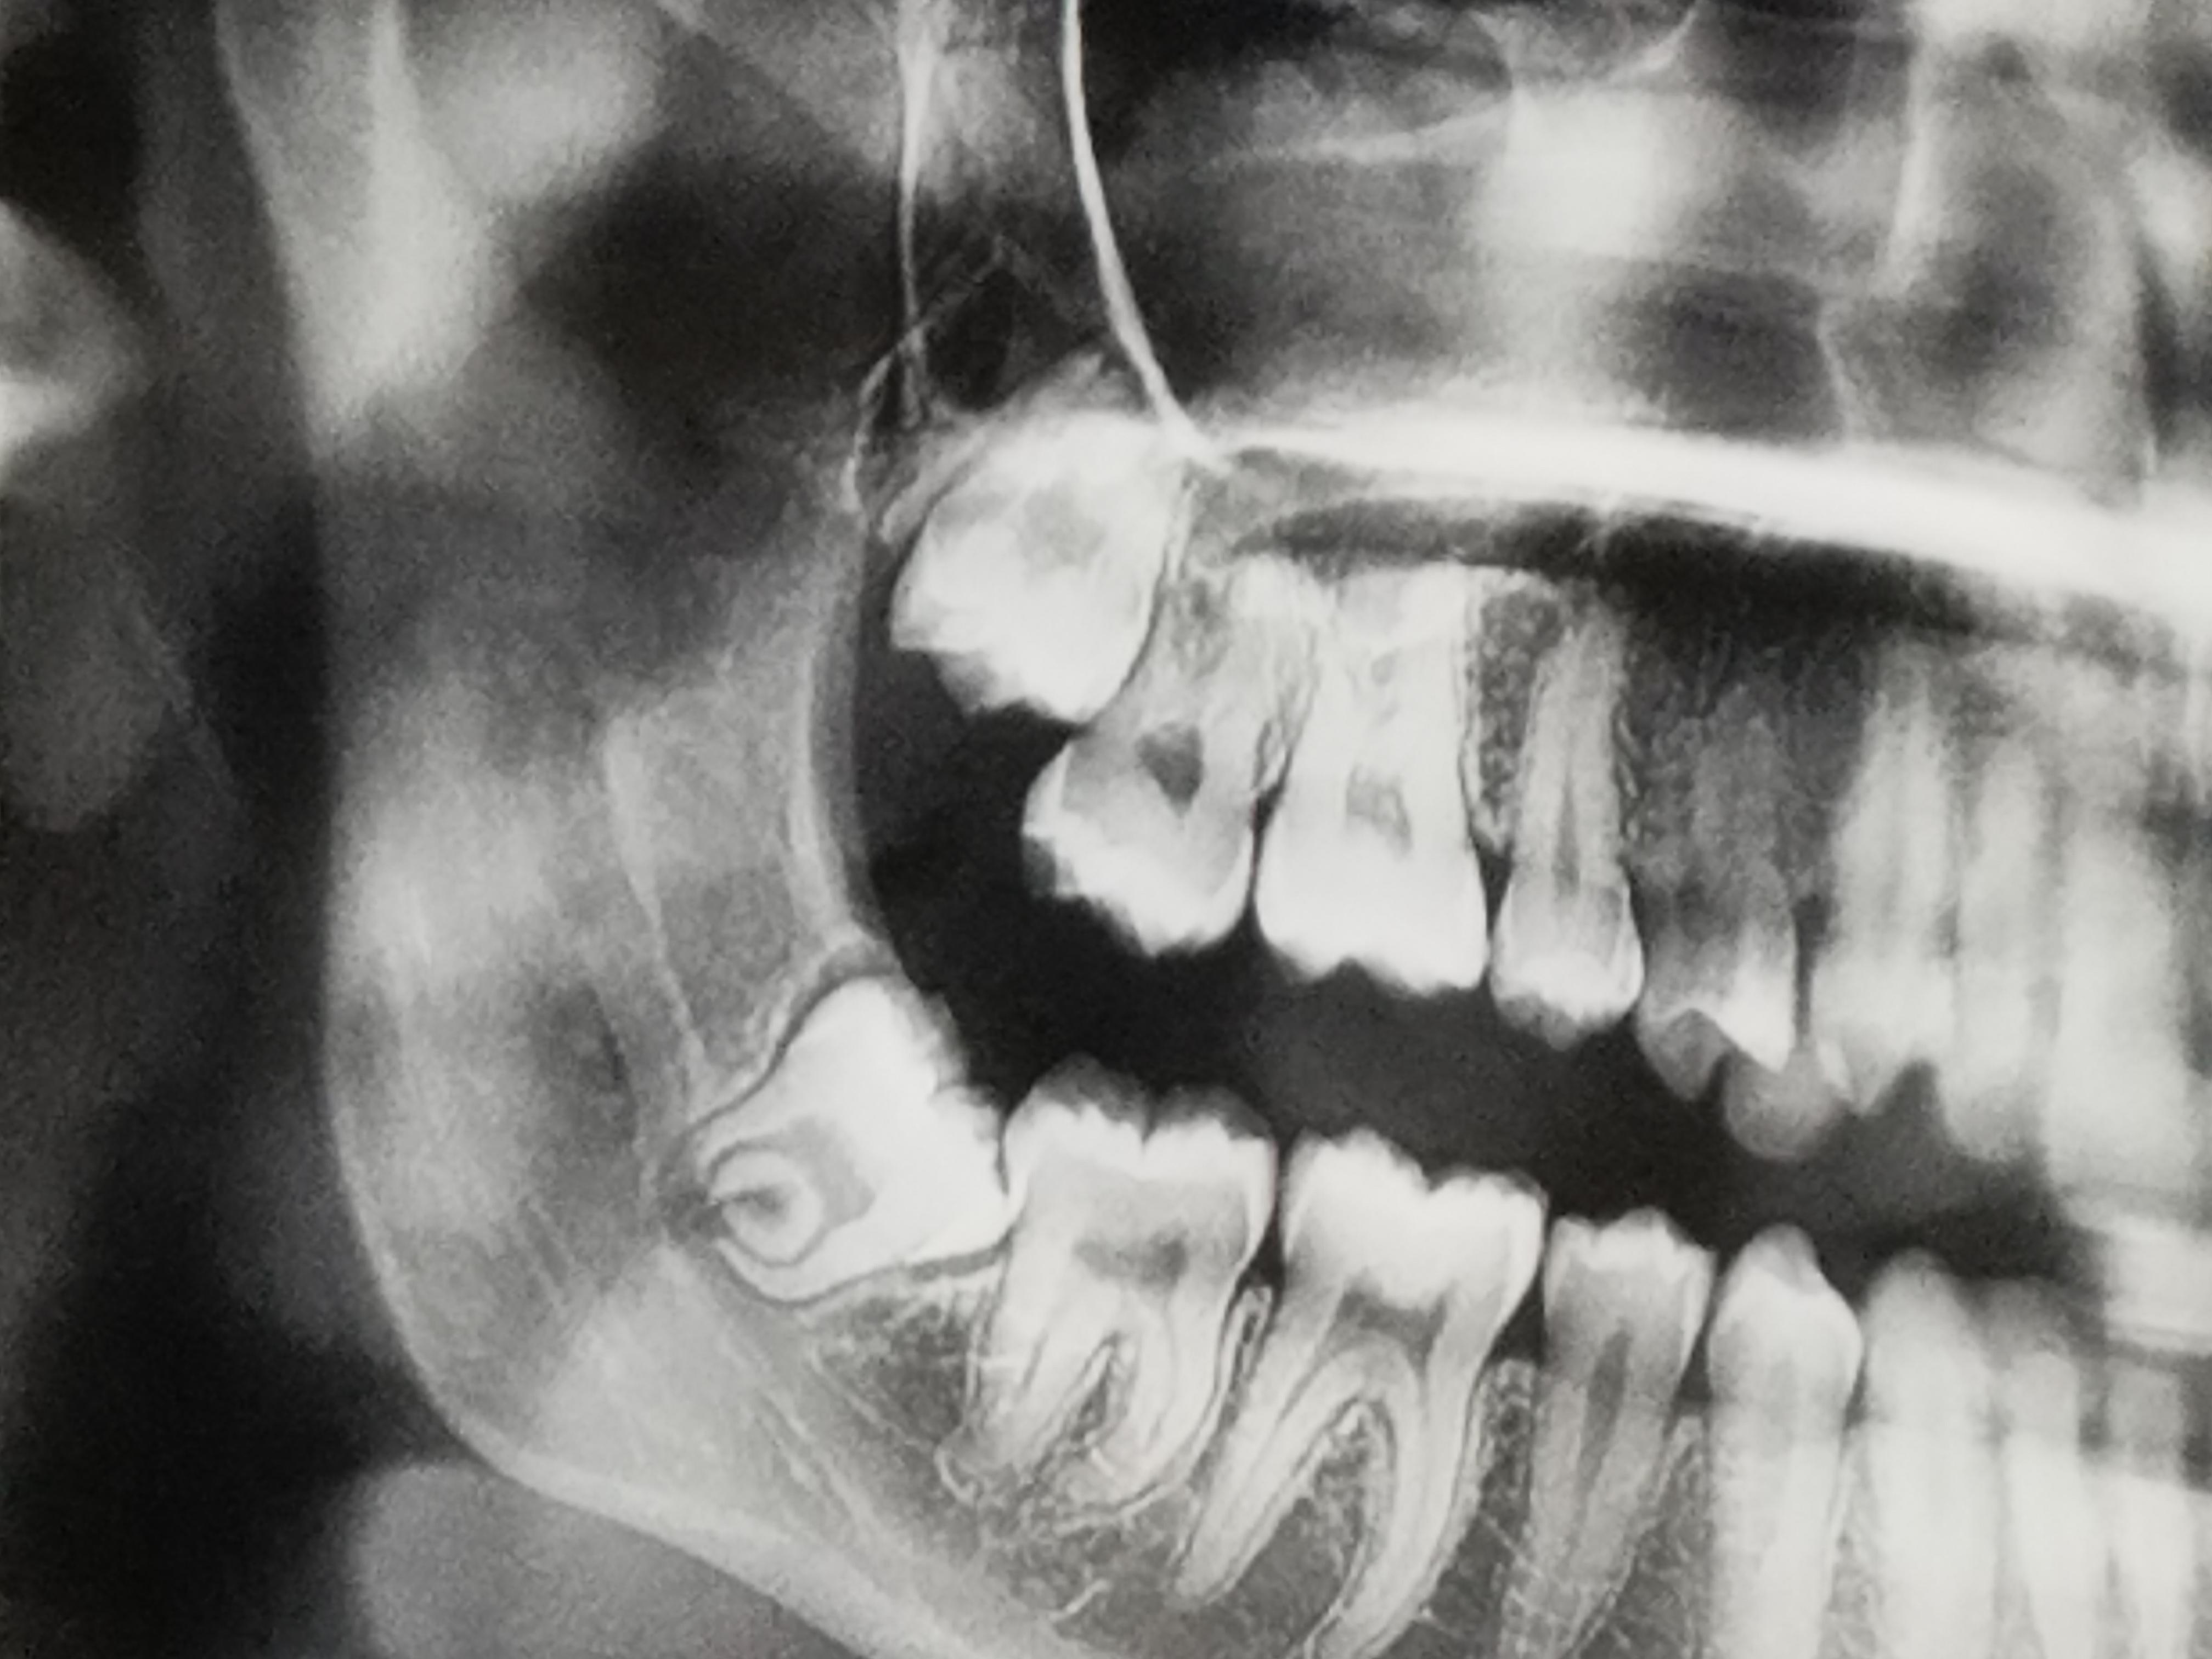

Web Wisdom teeth (third molars) become impacted because they don't have enough room to come in (erupt) or develop normally. Wisdom teeth usually emerge sometime between the ages of 17 and 25. Some.

WebIn addition, not all wisdom teeth grow straight or in the correct position. A condition when wisdom teeth grow into the other teeth is called impaction. Due to the commonality of.

Web Wisdom teeth grow at the right angle toward the other teeth; Like other teeth, they grow straight up and down but remain locked within the jawbone. Complications. A.

Web Also, wisdom teeth can grow in curved or at awkward angles that may cause them to become impacted. If this happens, your dentist will recommend having them.